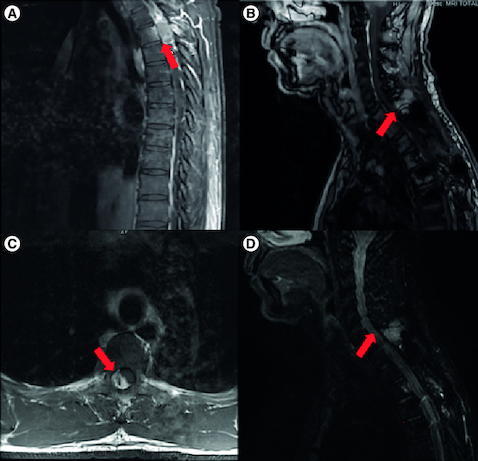

Atypical teratoid rhabdoid tumors (AT/RT) are rare and highly malignant CNS neoplasms primarily affecting children. Adult cases are extremely uncommon, with only approximately 92 reported. Spinal AT/RT in adults is particularly rare. Here, we present the case of a 50-year-old patient diagnosed with AT/RT of the spine. Initially, they were diagnosed and treated for a spinal ependymoma. However, after 10 years, a recurrence was detected through magnetic resonance imaging (MRI) and the tumor was reclassified as AT/RT. We discuss the significance of SMARCB1 gene mutations in diagnosing AT/RT and describe our unique treatment approach involving surgery, radiation and anti-PD1 therapy in this patient.